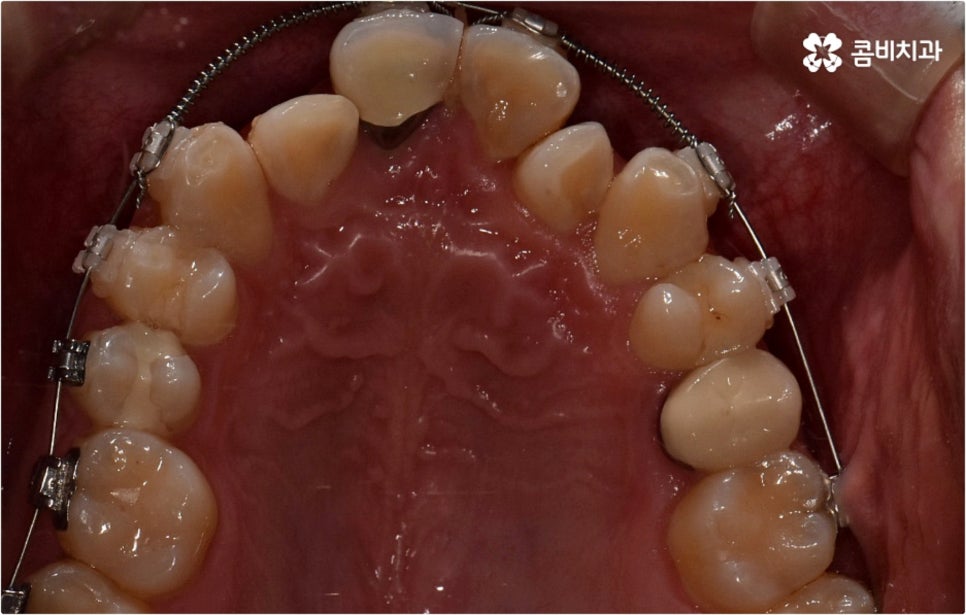

출처 아카이브 열기웃을 때 살짝 드러나는 덧니는 사람에 따라 매력 포인트로 느껴지는 경우도 있지만 구강 건강 측면에서 보면 치아와 치아가 겹쳐진 부분에 음식물 찌꺼기가 남아 치석이 쌓이기 쉽기 때문에 충치나 잇몸병이 더 자주 발생할 수 있으므로 주의하실 필요가 있습니다. 이와 같이 덧니는 옆 치아와 잇몸에까지 지속적으로 좋지 않은 영향을 주기 때문에 개선해 주는 게 좋은데요, 특히 덧니의 개수가 많아 삐뚤빼뚤한 정도가 심하다면 교합이 잘 맞지 않아 씹기가 불편하거나 턱관절 압박, 통증 등을 유발할 수 있으며 나아가 안면비대칭으로 이어질 수 있기 때문에 방치하지 말고 될 수 있는대로 빨리 덧니교정 을 통해 이를 바로잡아 주시길 권유드리고 있습니다.

덧니교정 시 환자분들의 상황에 따라 치아 이동에 필요한 공간이 부족하지 않다면 비발치 교정이 가능한데요, 이런 경우 치아 사이를 살짝 갈아서 여유 공간을 만드는 치간 삭제 방법, 마지막 어금니를 후방으로 이동시키는 방법, 그리고 악궁 확장 장치를 사용해 치아 사이를 벌려주는 방법 등 다양한 방법으로 공간을 만들어 치열을 가지런하게 바로잡아 줄 수 있습니다. 이때 환자분들의 구강 상태, 즉 악궁 크기 대비 치아의 크기, 치아가 겹친 정도, 덧니의 위치와 개수 등을 자세하게 검진한 다음 치아가 이동할 충분한 공간이 확보되지 않는다면 발치 교정을 하게 될 거예요.